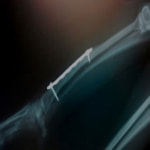

症例3:キルシュナーワイヤーのピンニングによる整復

ペルシャ猫 11ヶ月齢 雄

他院にて左大腿骨遠位の成長板骨折(salter-harrisⅠ型)が認められており、治療相談を目的として来院。当院にて、キルシュナーワイヤーを用いたピンニングにより骨折部位の整復を行いました。術後の経過は良好で、現在も経過観察中です。

術前レントゲン

術後レントゲン

機器

Arthrex社のターゲティングデバイスを用いてピンニングの位置を調整することで、確実な固定を行っています。当院ではこの手術器具以外にも、人の手術にも使用される様々な器具を導入し、手術精度を高め、また医療メーカーと新しい器具の開発、試作にも取り組んでおります。